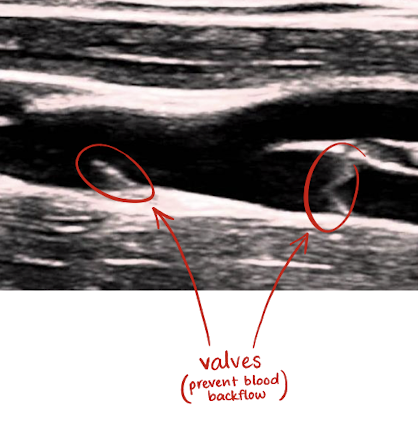

veins vs. arteries

veins carry blood back to heart

veins have thinner walls than arteries because they handle lower blood pressure

only veins are collapsible due to lack of elastic tissue and contain valves

arteries carry blood away from heart

function of IVC

return deoxygenated blood to heart using valves in its low-pressure system

valves prevent retrograde or backflow of blood during diastole